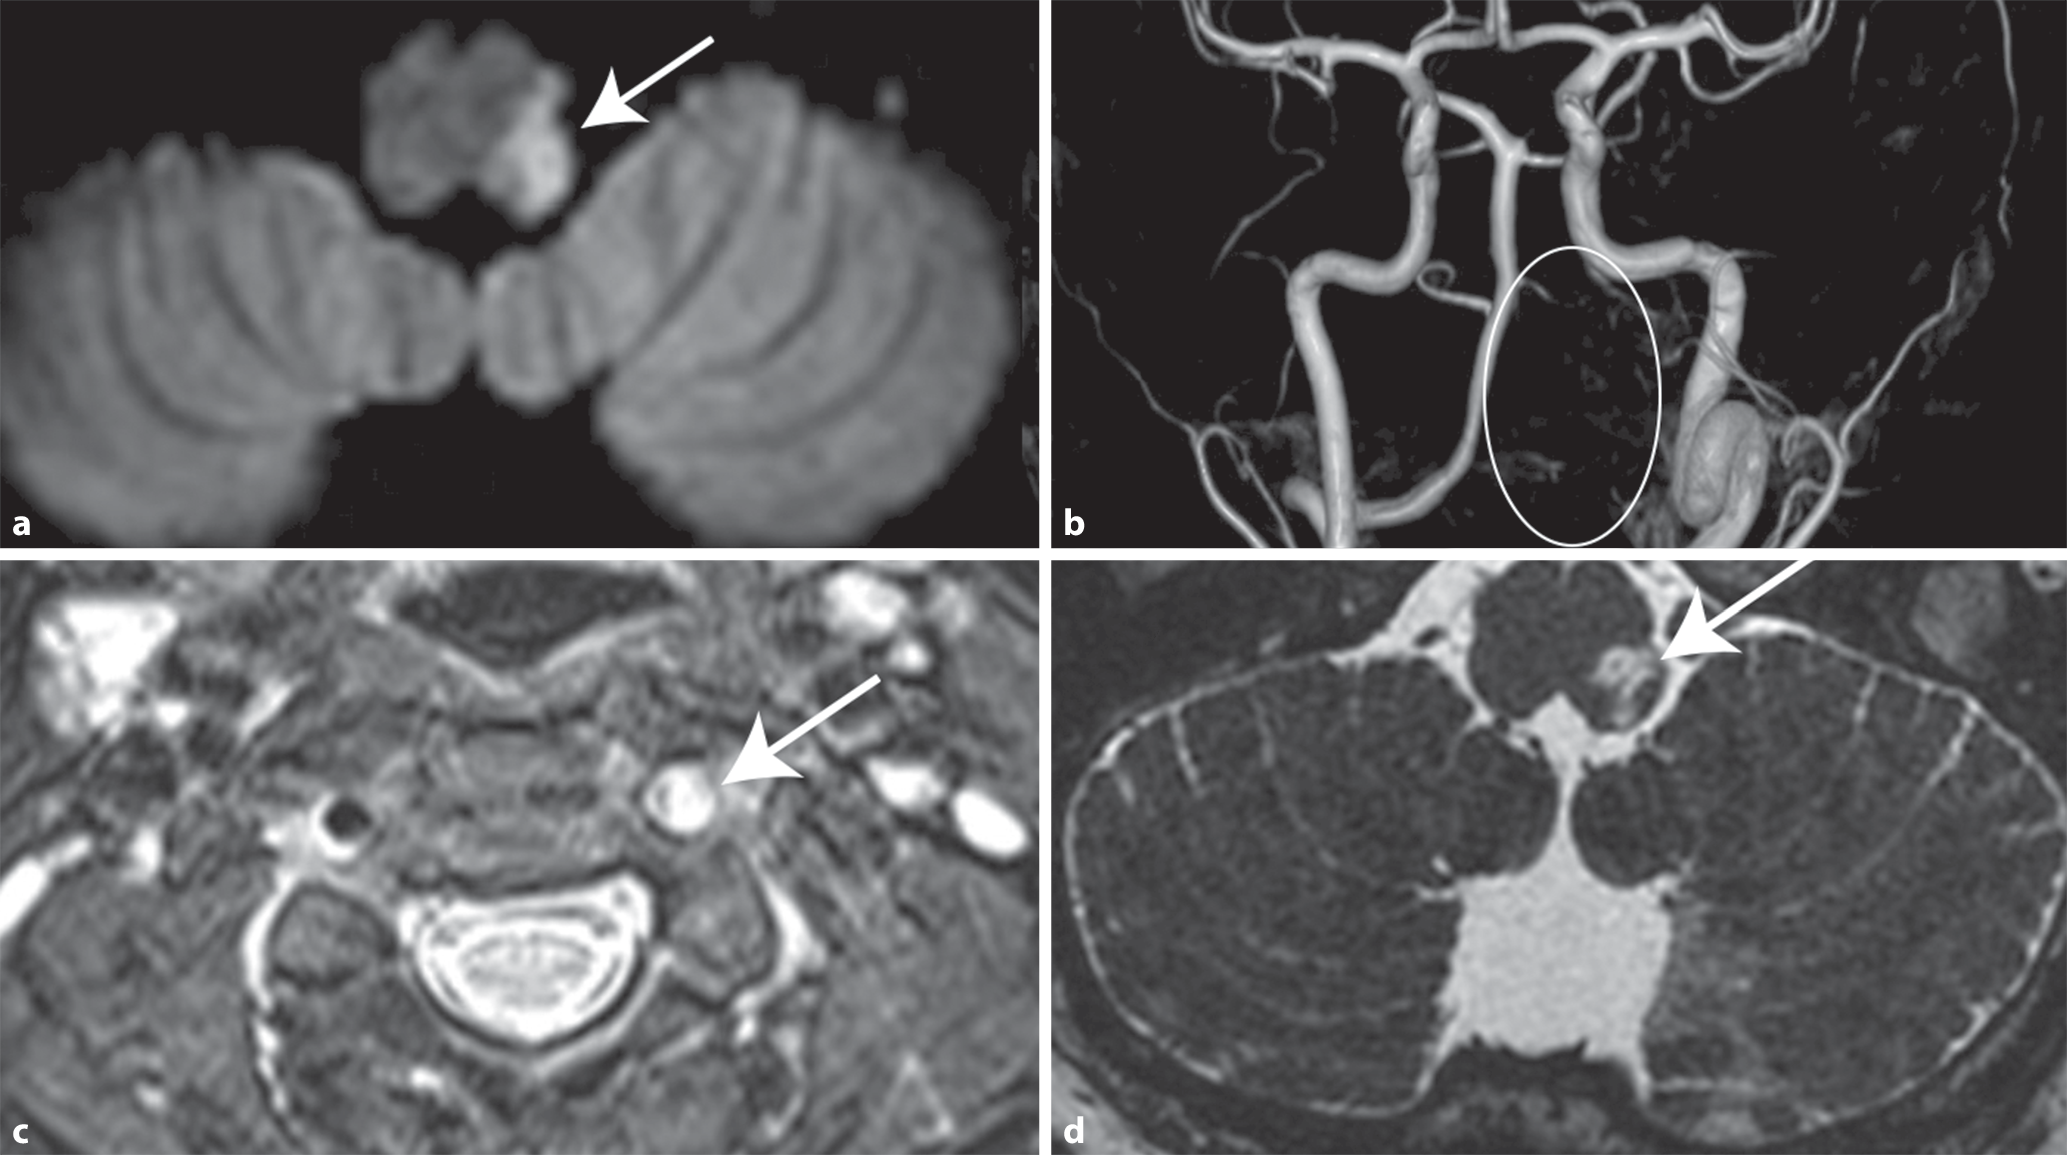

Eine bis dahin gesunde, 46-jährige Patientin wurde gegen 5 Uhr morgens mit einer akut aufgetretenen Schluckstörung, anhaltendem Schwankschwindel, Fallneigung und Doppelbildern mit dem Rettungsdienst auf die Notfallstation gebracht. Bereits ca. 5 h zuvor hatte sie einen plötzlich einsetzenden Drehschwindel, Übelkeit, Erbrechen und Durchfall bemerkt. In der initialen klinisch-neurologischen Untersuchung zeigten sich Auffälligkeiten der Okulomotorik (nach oben schlagender Spontannystagmus, horizontal eingeschränkte exzentrische Blickhaltefunktion [sog. Blickrichtungsnystagmus]), eine Ptosis links mit Anisokorie (links < rechts), eine Mundastschwäche, eine leichtgradige Gaumensegelparese links, eine Koordinationsstörung des linken Arms im Finger-Nase-Versuch, eine ausgeprägte Fallneigung nach links und ein arm- und beinbetontes vermindertes Temperaturempfinden rechts. In einer umgehend erfolgten zerebralen Computertomographie (CT) einschließlich CT-Angiographie ließ sich ein Verschluss der linken A. vertebralis im V2- bis V4-Segment (bis kurz vor Abgang der PICA) nachweisen (vergleiche auch Abb. 2b). Eine Blutung oder Raumforderung fand sich nicht. Die CT-Perfusion war negativ. Es wurde eine antiaggregatorische Therapie mit Azetylsalizylsäure (initial „loading“ mit 500 mg i.v., dann 100 mg/Tag) begonnen, und die Patientin wurde zum Monitoring und zur weiteren Diagnostik auf die Stroke-Unit aufgenommen. In der MRT des Schädel ließ sich eine akute Diffusionsrestriktion in der dorsolateralen Medulla oblongata links nachweisen, passend zu einem Wallenberg-Syndrom (Abb. 2a). Die MR-Angiographie mit Dissektionsprotokoll bestätigte eine spontane Dissektion in der linken Vertebralarterie im V2- bis V4-Segment (Abb. 2c). Nach 4 Wochen ließ sich in der MRT der aufgetretene Substanzdefekt deutlich nachweisen (Abb. 2d). Bei Abschluss der stationären Neurorehabilitation nach 2,5 Monaten hatten sich die klinischen Befunde bis auf die Temperatursinnstörung der rechten Körperseite nahezu vollständig normalisiert.

Abb. 2

Zerebrale Bildgebung (Fallbeispiel) im Akutstadium (a–c) sowie im Verlauf nach 4 Wochen (d), a axiale diffusionsgewichtete (DWI) Sequenz mit Nachweis eines akuten Infarkts (Pfeil) im Bereich der linken dorsolateralen Medulla oblongata, b MR-TOF-Angiographie (MR-: Magnetresonanz-; TOF: „time of flight“), dabei Nachweis einer links fehlenden A. vertebralis im Bereich der Markierung (Kreis), c axiale T2-gewichtete fettsupprimierte Sequenz (sog. Dissektionsprotokoll) mit Nachweis eines die linke Vertebralarterie komprimierenden Wandhämatoms (Pfeil), d axiale hochauflösende T2-Sequenz mit Nachweis einer subakuten Läsion in der links-lateralen Medulla oblongata (Pfeil), Aufnahme 4 Wochen nach Symptombeginn